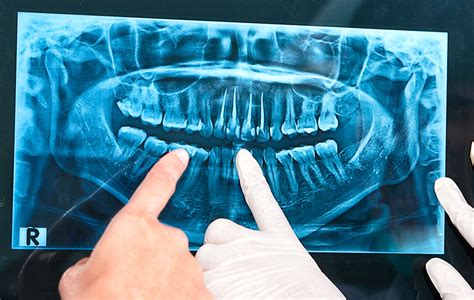

Son las que se toman fuera de la boca. Suelen realizarse con máquinas grandes en salas plomadas dentro de la clínica dental. Sirven para valorar de manera global el conjunto de los dientes, hueso y estructuras. Este tipo de Rx incluye las radiografías panorámicas o ortopantomografías o el TAC Dental 3D (para planificación de implantes dentales).

¿Qué Podemos Observar en las Radiografías Dentales de Niños?

Es muy importante que el odontopediatra o dentista de niños diagnostique la causa de problemas como la permanencia prolongada de un diente de leche mediante una radiografía.